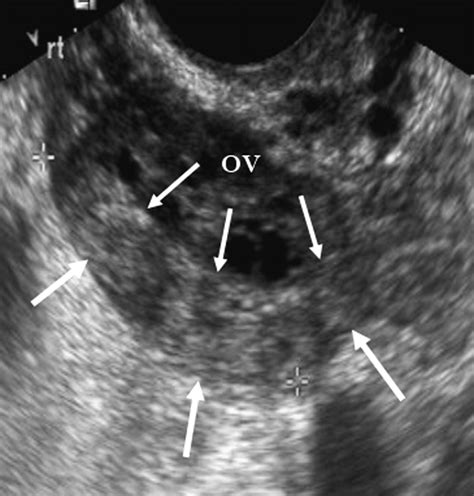

An ovary normal ultrasound refers to findings where the ovaries appear within expected physiological parameters based on your age and hormonal status. During the scan, a sonographer or radiologist examines the size, shape, volume, and echogenicity of both the right and left ovaries. They are specifically looking for the presence of follicles, the absence of suspicious masses, and correct positioning within the pelvis.

In a healthy, pre-menopausal individual, the ovaries are typically almond-shaped and vary in size throughout the menstrual cycle. The presence of small, fluid-filled sacs called follicles is entirely normal, as these represent eggs in various stages of development. A normal report confirms that these structures are present without evidence of complex cysts, solid tumors, or other indicators of pathology.

• Echogenicity: This refers to how the tissue reflects sound waves. Normal ovarian tissue has a characteristic texture that allows sonographers to distinguish it from surrounding structures like the bowel or bladder.

• Follicular Pattern: The presence of multiple small, uniform follicles (often described as "antral follicles") is a sign of normal ovarian reserve and function.